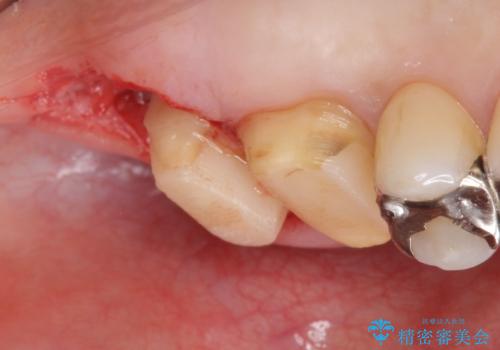

- 銀歯をやりかえたいが他院で抜歯と言われセカンドオピニオンで来院。適合の悪い被せ物が入っており、まずは古い材料、虫歯をとり保存可能か確かめる必要があり、拡大鏡下で全て取り除いたら歯質が歯茎の中まで虫歯がありました。このまま無理やり型取りをして被せ物を作っても不適合な被せ物が入る可能性が高いため歯茎を切り取る手術(ディスタルウェッジ)を行いました。そして再根管治療を行いゴールドの被せ物で治療を行いました。